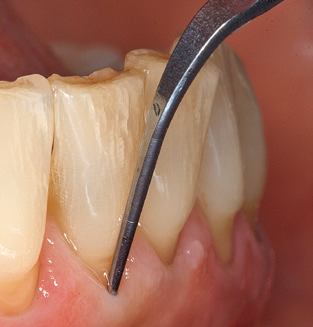

Una buona illuminazione del campo di lavoro facilita notevolmente il processo. Il sistema utilizzato dagli autori ottiene questo risultato grazie a un anello LED 5x integrato nel manipolo. Naturalmente, viene offerta anche una serie di consigli di lavoro per diverse indicazioni. Un inserto diritto, utilizzabile universalmente, è lo strumento di base necessario per la pulizia meccanica dei denti naturali (Fig. 5a e b). Sono disponibili anche inserti curvi, che consentono l'accesso alle forcazioni esposte, per le aree difficili da raggiungere nella regione posteriore (Fig. 6).

Naturalmente, anche i consigli di lavoro per la pulizia delle superfici degli impianti sono indispensabili per SPT nei pazienti dotati di impianti. L'inserto per la pulizia dell'impianto in questo casoi è caratterizzato dal suo design affusolato ed esagonale. Questo design consente una penetrazione leggera e atraumatica nella tasca perimplantare e mostra buone prestazioni di pulizia (Fig. 7).